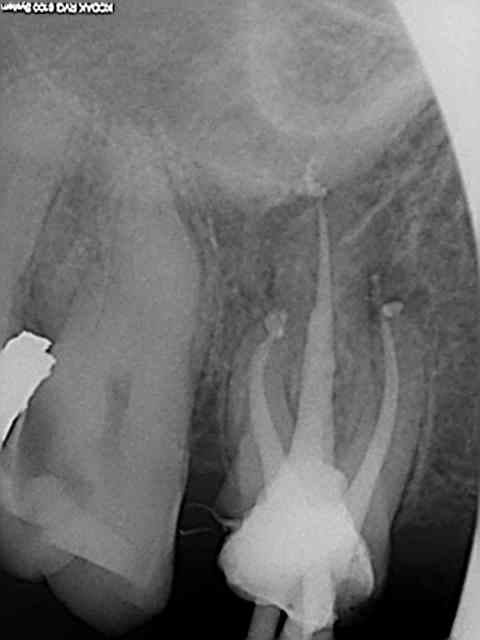

je pense qu'il serait bon de voir la rx de cette fameuse dent.

si elle présente effectivement un problème apical , la mutuelle va bien involontairement éviter à ce confrère des emmerdements en cas de contrôle d'activité!

> je pense qu'il serait bon de voir la rx de cette fameuse dent.

> si elle présente effectivement un problème apical , la mutuelle va bien

> involontairement éviter à ce confrère des emmerdements en cas de contrôle

> d'activité!

Ah bon ?

X ray 03 medium zvq18j - Eugenol